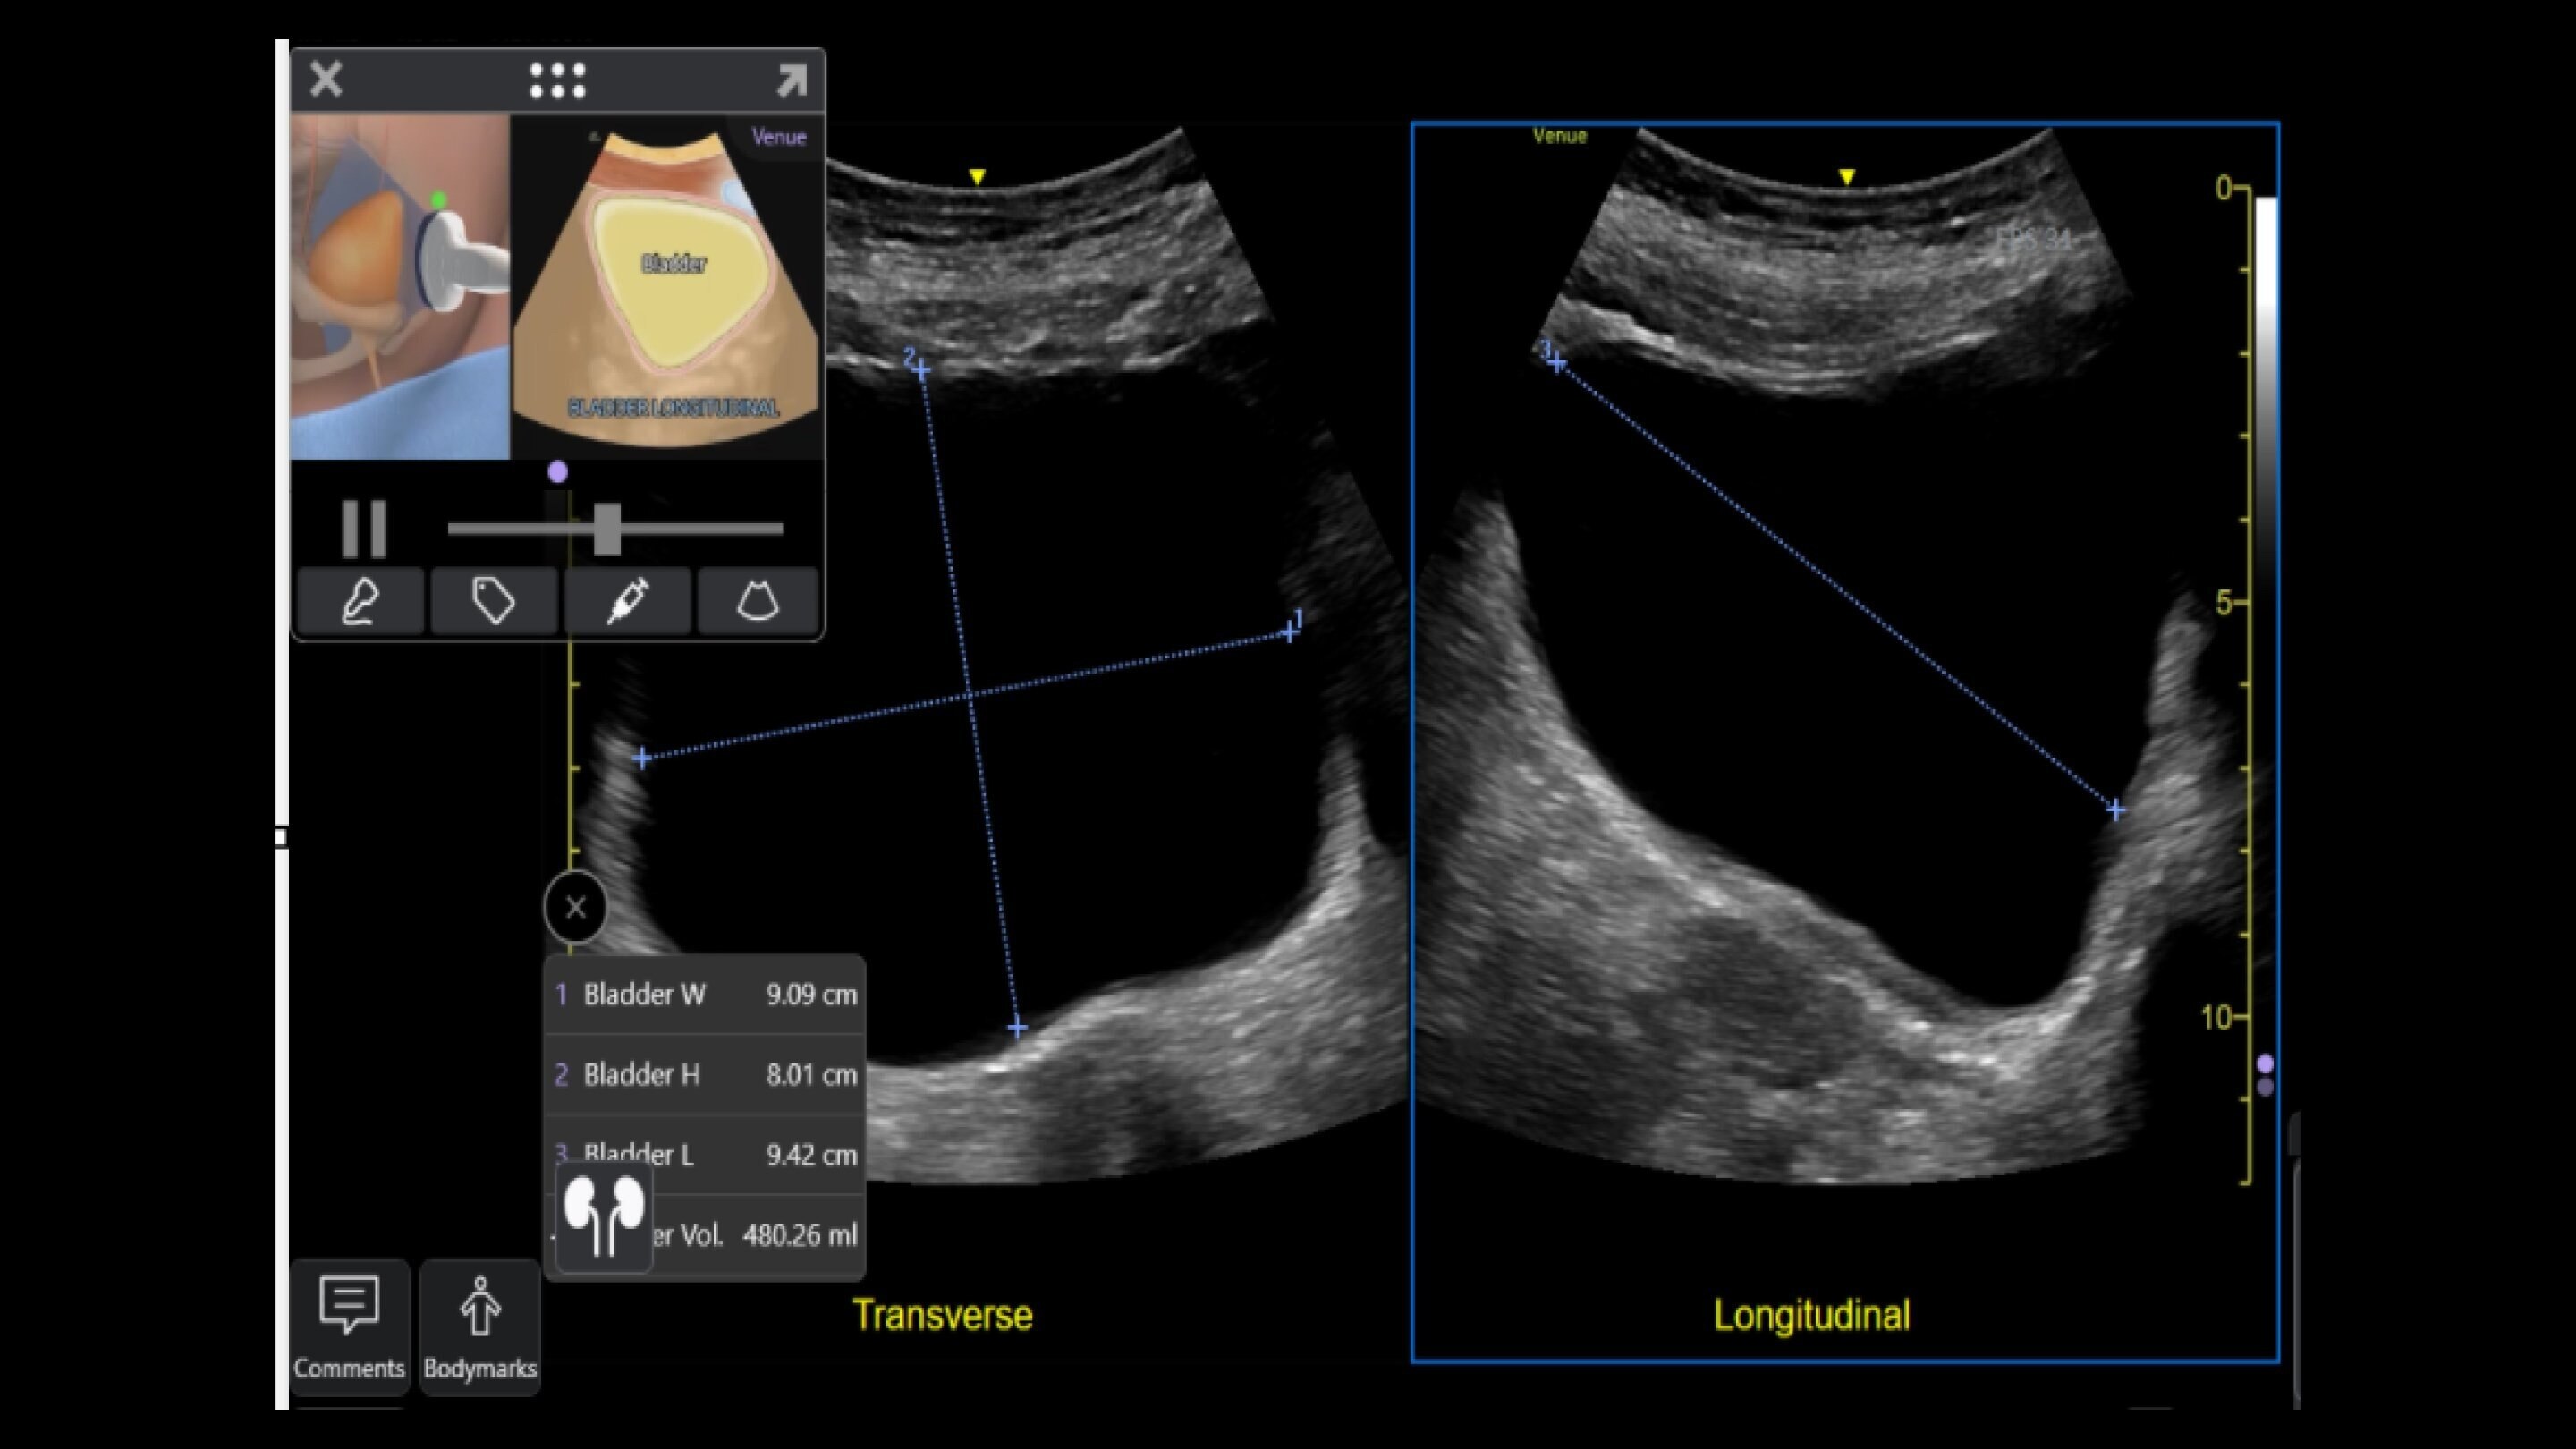

Venue Sprint™ gives you the uncompromised image quality and smart workflow of Venue™ family systems along with the freedom and maximum portability of wireless probes. This all-in-one, entry-level solution combines wireless connectivity with a small, streamlined console. It features Venue family software, to give you access to the AI tools you need, to simplify advanced exams whenever and wherever care is needed.

With the portability and mobility to go anywhere, you can get ahead with Venue Sprint. Take handheld ultrasound to different clinical spaces, sync up and be ready to go. Venue Sprint supports a wide range of environments including:

Critical care

Enables on-the-spot visual confirmation, aiding the team in decision-making and collaboration on complex cases.